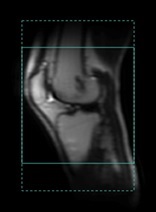

| 4 | When a No Phase Wrap factor greater than 1.0 is selected and the Show No Phase Wrap option is selected from the Graphic Rx Tools menu, the extent of the No Phase Wrap is displayed with dotted lines. This provides a visual guide so that you can select a factor that extends larger than the anatomy. The Show No Phase Wrap state is retained between exams and system reboots. ![]() |